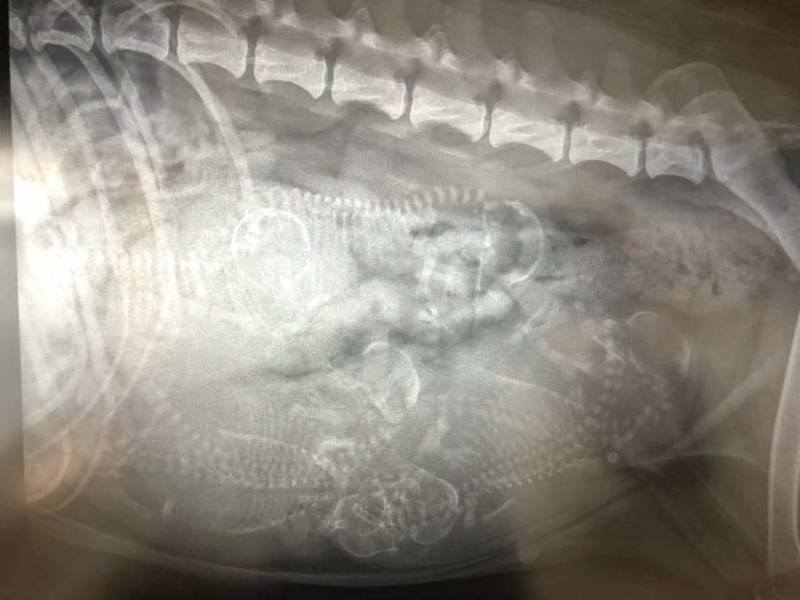

18-01-2019

Röntgenfoto.